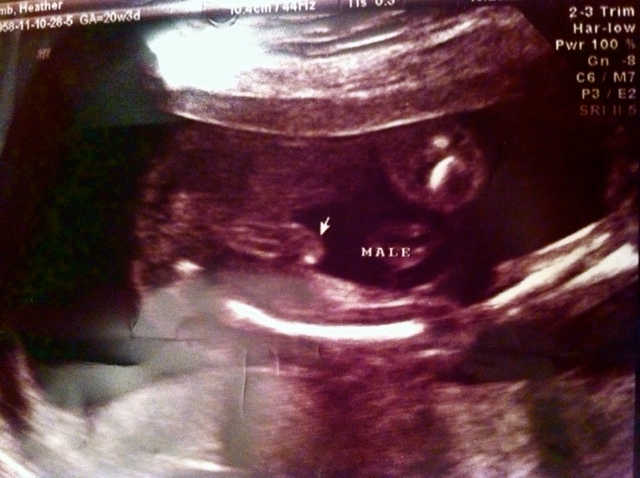

Here is Noah at my 20 weeks appointment...

Here's his weewee! He's a boy! See?